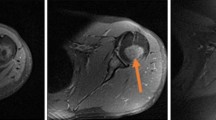

The main objective of this study was to configure the acquisition and analysis of low-field magnetic resonance imaging (MRI) to predict physico-chemical characteristics of Iberian loin, evaluating the use of different MRI sequences (spin echo, SE; gradient echo, GE; turbo 3D, T3D), computational texture feature methods (GLCM, NGLDM, GLRLM, GLCM + NGLDM + GLRLM), and data mining techniques (multiple linear regression, MLR; isotonic regression, IR). Moderate to very good correlation coefficients and low mean absolute error were found when applying MLR or IR on any method of computational texture features from MRI acquired with SE or GE. For T3D sequence, accurate results are only obtained by applying IR on GLCM or GLCM + NGLDM + GLRLM methods. Considering not only the accuracy of the methodology but also consumed time and required resources, the use of SE sequences for MRI acquisition, GLCM method for MRI texture analysis, and MLR could be indicated for prediction physico-chemical characteristics of loin.